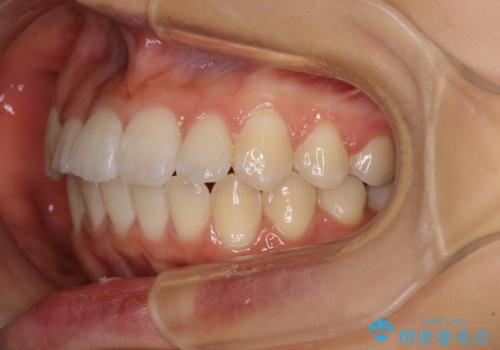

- 上下のデコボコと前歯のクロスバイトを改善したいとのことで来院された患者様です。

極力短期間で治療したいとのことで、ワイヤー装置による矯正治療を行うこととしました。

お住まいが遠方であったため、マウスピースによる矯正治療も提案しましたが、ご自身でのマウスピースの管理の面倒くささと、なるべく早く治療を終えたいとのことで、ワイヤー矯正を選択されました。